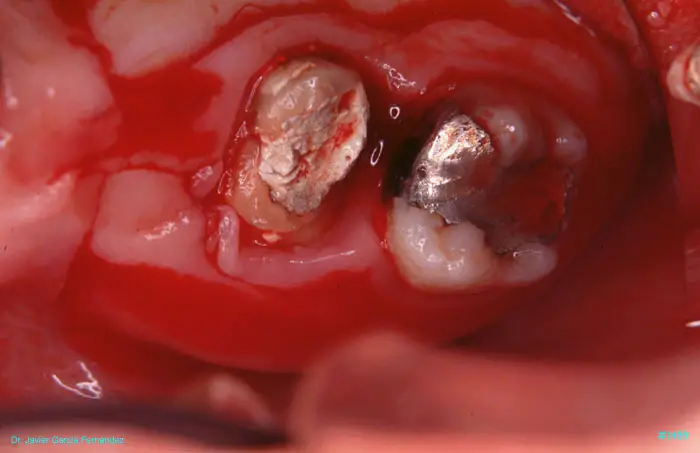

Atlas of Surgical Techniques in Periodontics. Chapter III. Atlas de Técnicas Quirúrgicas en Periodoncia